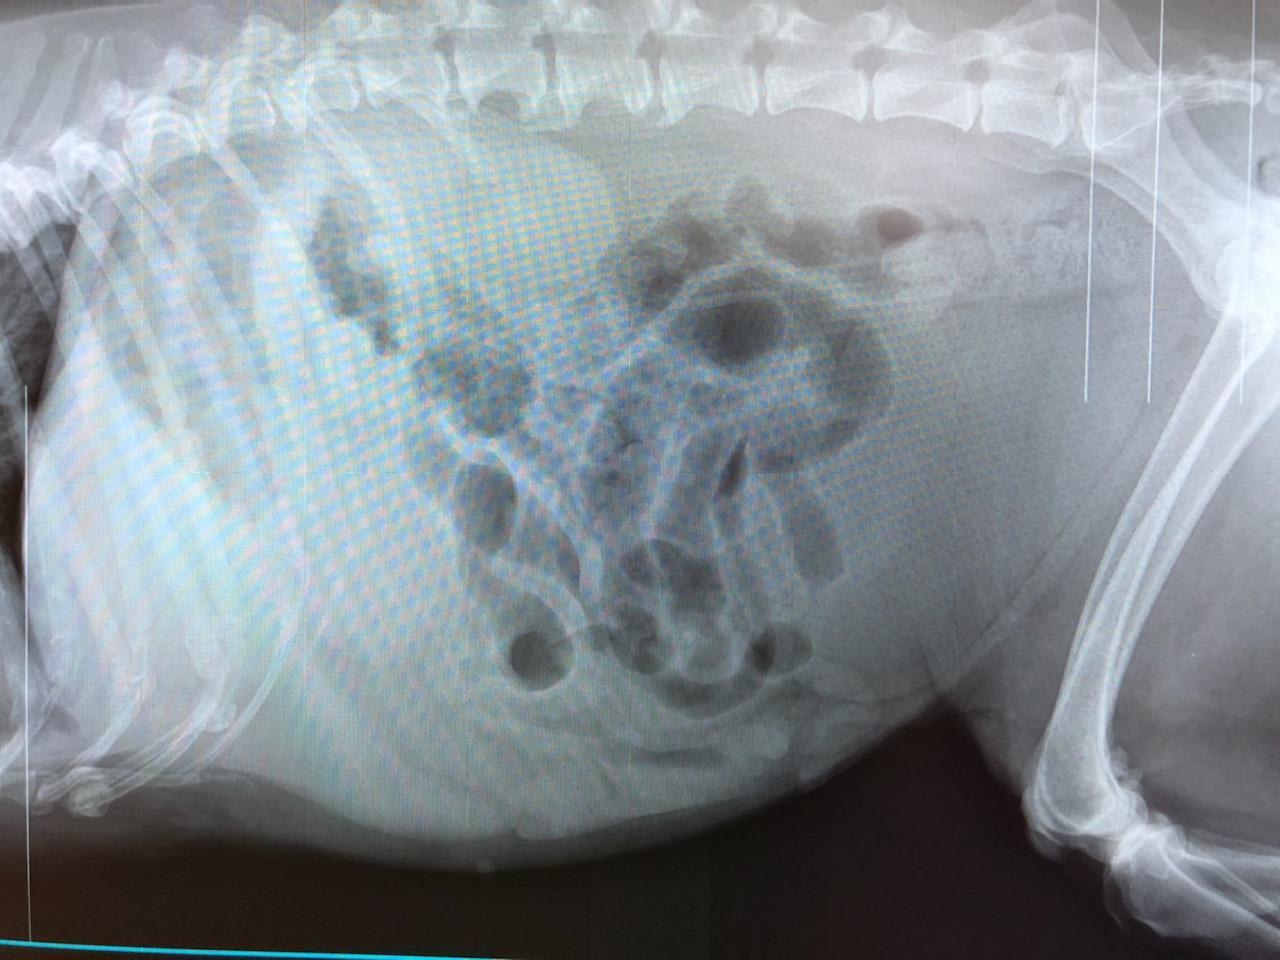

My mother's border collie 13yo was recently diagnosed with diabetes. Due to her not eating my mother took the dog to the vet, x-rays were taken which showed an enlarged liver with mass and blocked bile ducts. Per the vet the dog was so swollen due to gas that the kidneys could not be seen on the x-rays. Her blood sugar was 500. The vet advised that due to her unstable condition that her chances of survival are low for a mass removal. Should we try surgical intervention, or humane euthanasia :'(

Hello. Without the bloodwork, I can not address her overall condition to say whether surgery is appropriate or not. I would highly recommend that x-rays of her lungs be done to see if there is any evidence that the mass on her liver has metastasized to her lungs. If this has happened, then I would not put her through surgery. An ultrasound of her abdomen would also be very useful in looking at the liver, gall bladder & kidneys, & would give much more information about what is going on. In the meantime, I would start her on insulin to try & regulate the elevated blood sugar. Talk to your vet to see what the next best steps for Layla are. Thanks for contacting Petco Pet Education Center, formerly Petcoach.